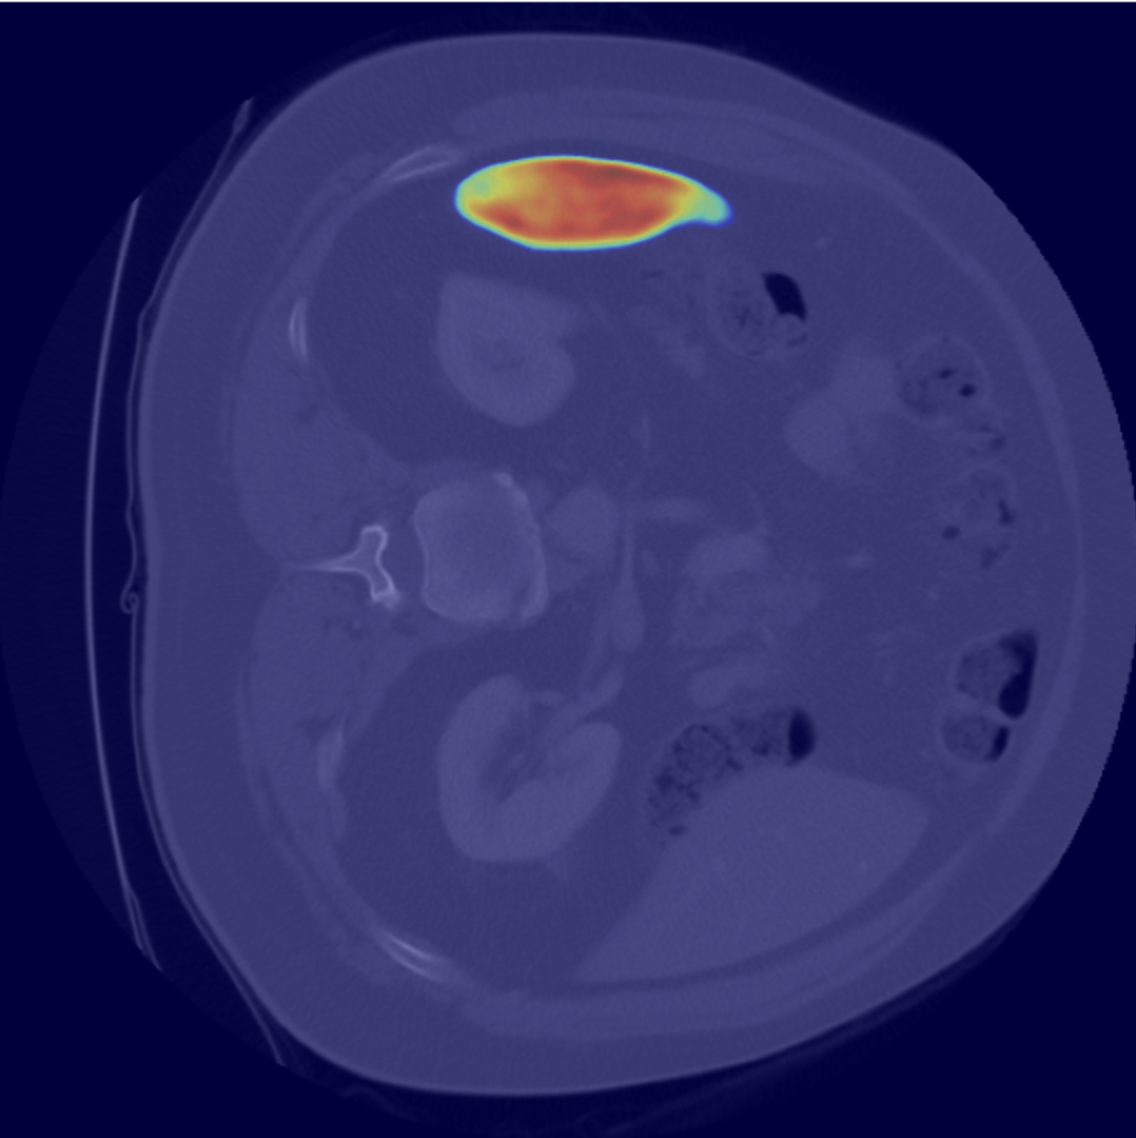

EU-Nets consistently outperform their baseline counterparts, particularly in terms of stability, demonstrating robustness across different cross-validation folds and diverse data distributions. Moreover, integrating MHEX+ introduces only a minimal increase in model parameters (<0.1M). For overall performance comparison, see Table 4, and for individual sample results, refer to the Pred row in Figure 4.

Although both MHEX+ and Grad-CAM highlight important regions, they rely on fundamentally different mechanisms. Grad-CAM computes pixel-wise gradients, reproducing the segmentation output rather than providing deeper insights.

In contrast, MHEX+ leverages class-level equivalent convolution kernels to analyze how the network attends to each class. By aggregating learned weights instead of focusing solely on pixel-level gradients, MHEX+ captures multi-scale feature responses across decoder stages, highlighting relevant regions beyond the segmented target, such as liver and kidney areas. For comparison, see Figure 5.

To evaluate the validity of our MHEX+ based uncertainty estimation (MU), we compare MU maps with Deep Ensemble uncertainty (DEU) maps (Section 3.5).

We conducted experiments on the MSD-Heart dataset using 50 randomly selected samples and tested four proposed EU-Nets. Each model’s uncertainty was computed via the MU approach, and the resulting maps were aggregated into a single composite visualization (Fig. 6, last column). For single uncertainty samples, see Figure 4, last row. DEU maps (Fig. 6) were obtained using entropy- and variance-based uncertainty estimation (Section 3.5).